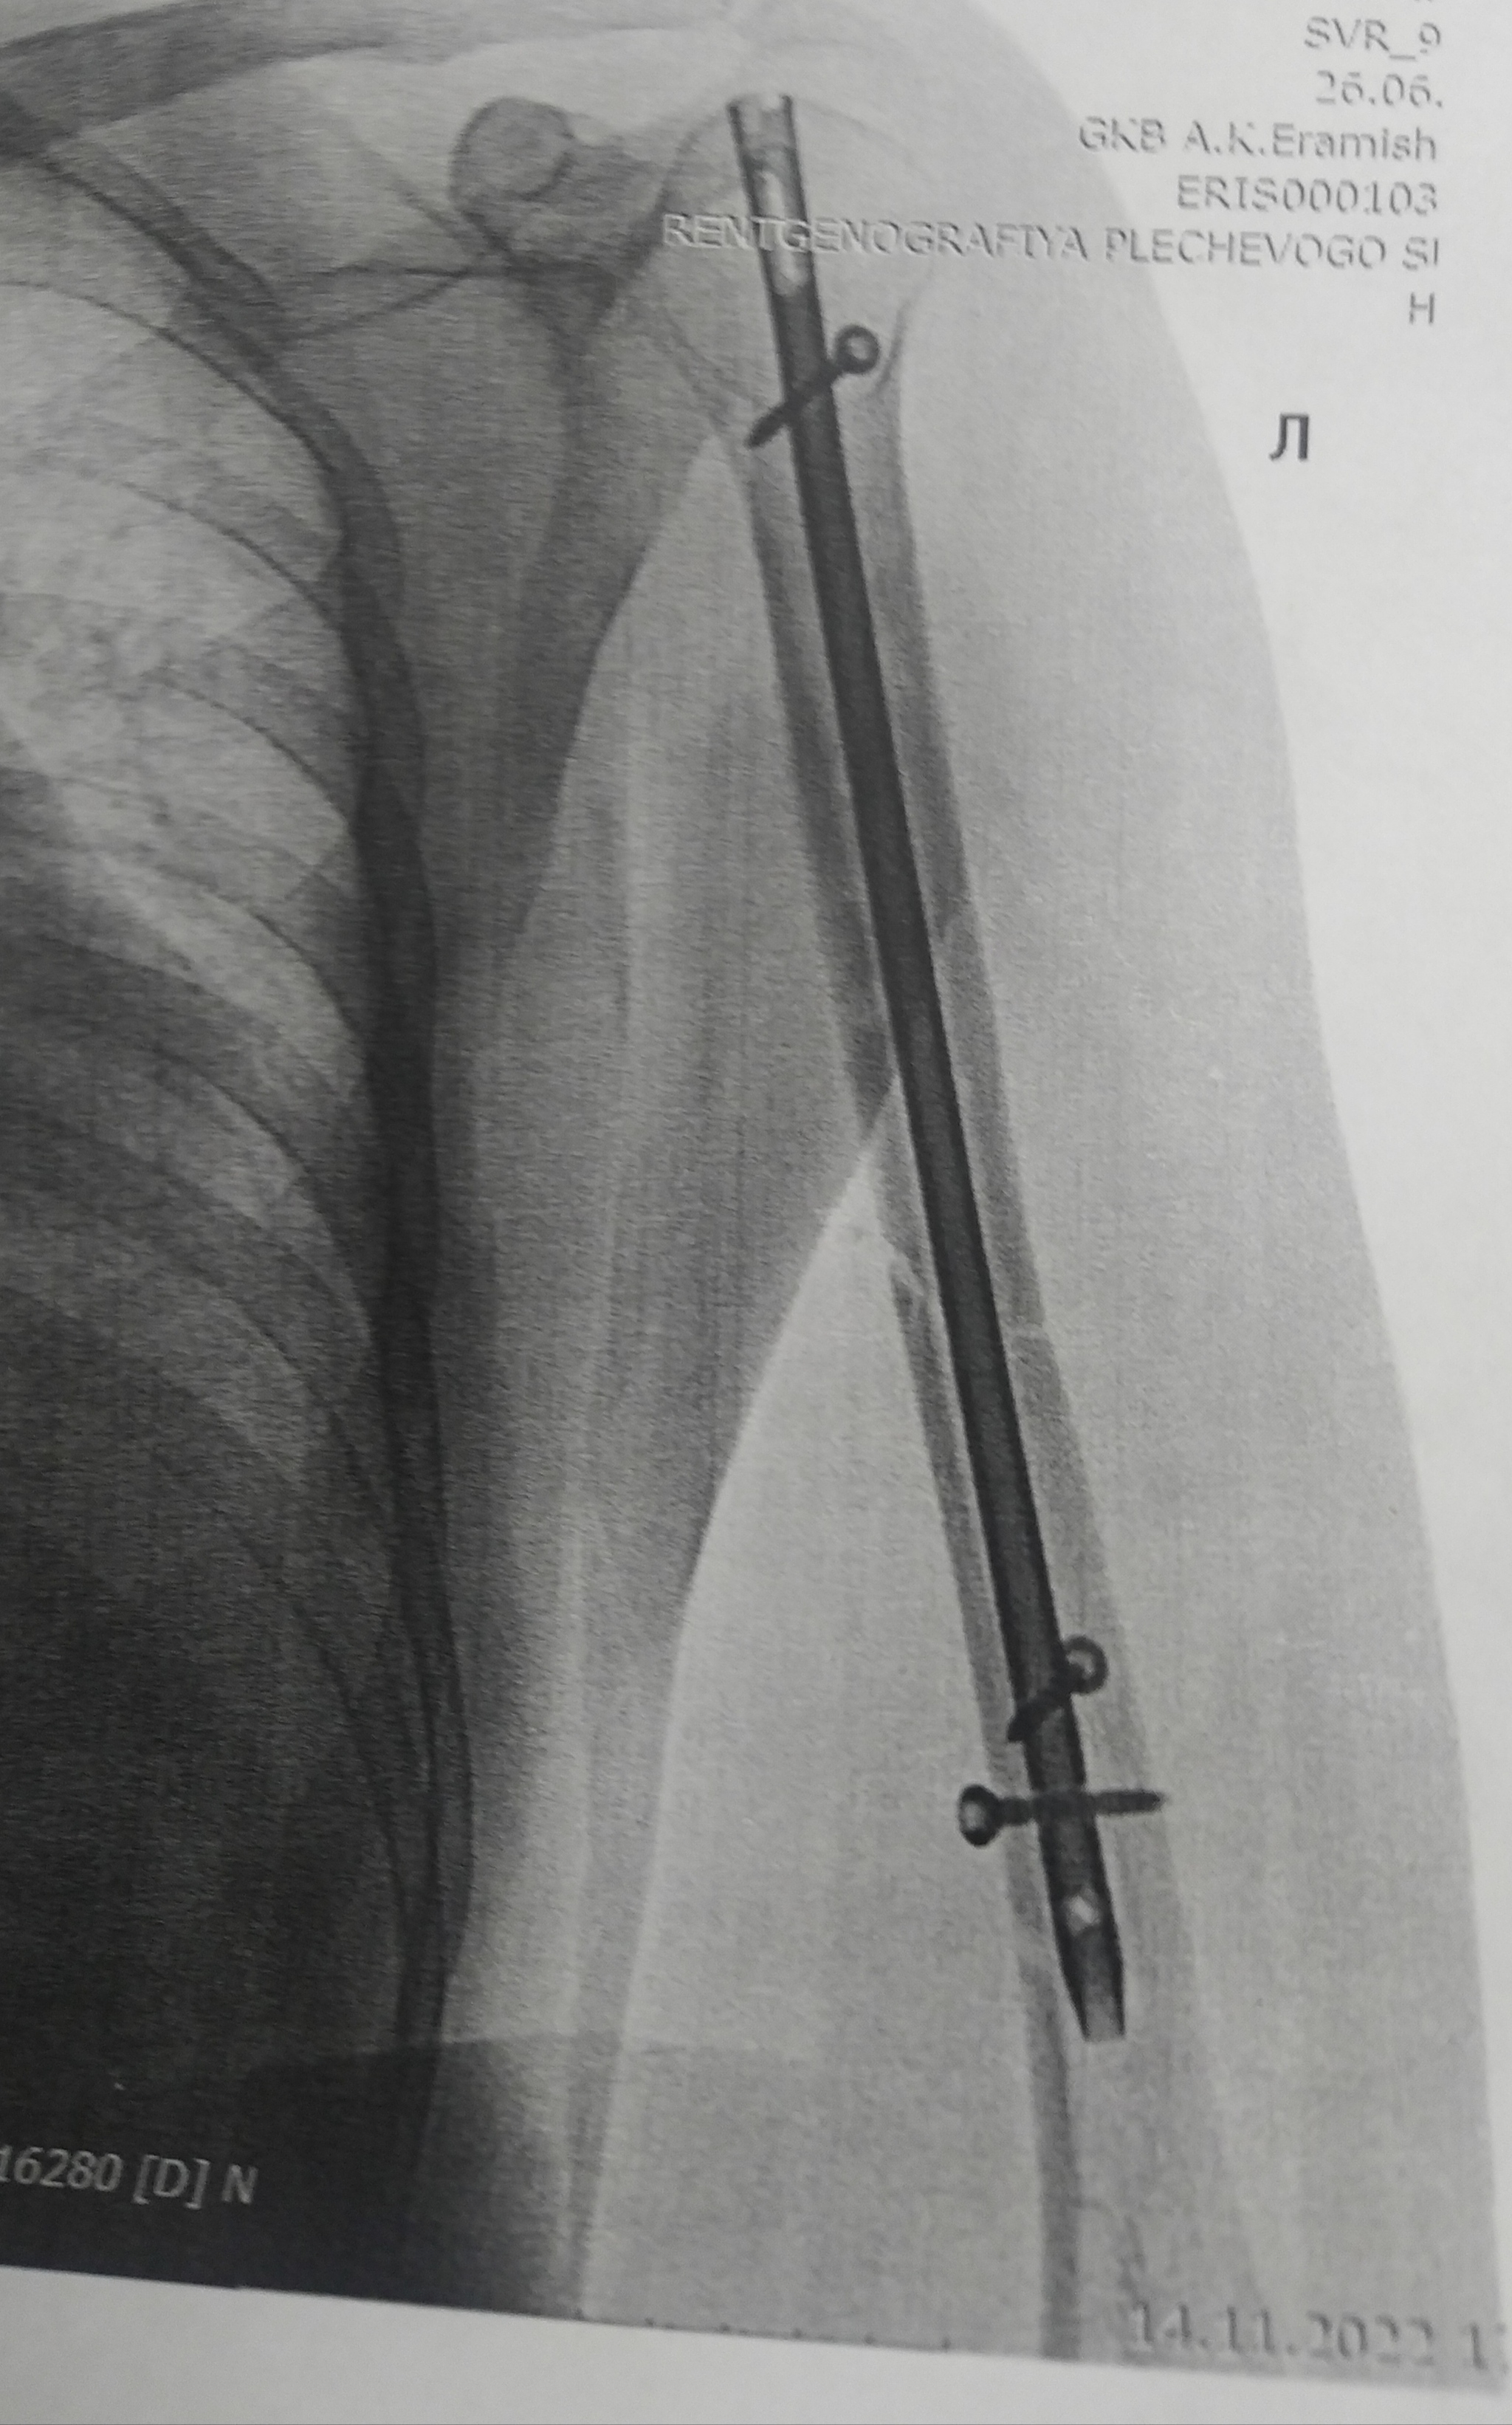

У меня ДТП. Я за рулём, на меня на встречку вылетел лоб в лоб. Очнулся в больнице. Левую ногу и левую руку собирали. Вот на руке шрам страшный. Из последствий нога короче на 3см. Спец обувь. А так, спустя 1,5 года всё отлично)))) но металл пока во мне. Не знаю, буду вынимать или нет. И так натерпелся операций, не хочу....

Ох, некисло. У меня тоже дтп, тоже на меня влетели на встречке, я тоже водитель. Дед, который в меня влетел, сразу зажмурился. В моем авто погиб человек, второйс тяжелейшей чмт, третий с разрывом органов брюшной полости. Если бы не ремни безопасности (все были пристёгнуты) - точно бы погибли все четверо в моем авто. Самое страшное, конечно, это пробуждение в тачке через 15 минут после аварии. Очнулся - тачка вдребезги, всё в крови,я зажат, вокруг авто ходят люди с выпученными глазами, а мои пассажиры (к счастью) хотя бы смогли самостоятельно вылезти. Смотрю - бедро зажато сильно, боль невыносимая.... После того, как меня достали МЧС, в скорой мне кололи морфин. Боль была такая, что я тот морфин и не почувствовал... словно не кололи вовсе. Травматический шок 3 степени, блин...